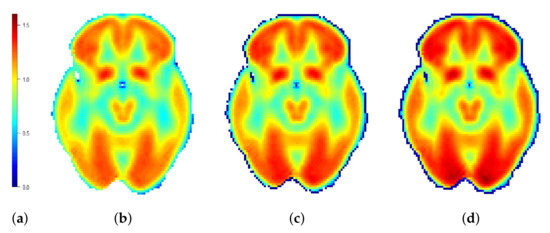

3.2. One-Group Mean Function and SCC Estimation

3.3. Two-Group Mean Function and SCC Estimation